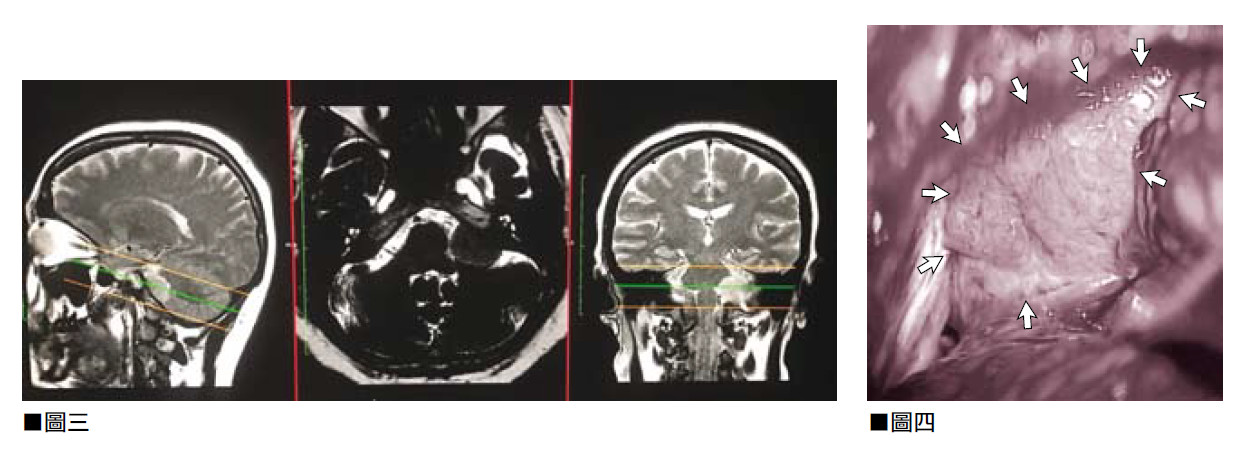

這是2015年的病例,一位來自中國內地50歲的女病人,症狀包括六個月的頭痛、視線模糊。從在中國做的磁力共振顯示,病人腦下垂顱底骨基部有2厘米的腫瘤,向腦上延伸和壓迫着視覺神經,在兩側亦包住雙側腦內主大動脈(ICA)和前大腦動(ACA)。(見圖一)

為她進行了六小時的微創開顱手術,在顯微鏡下將腫瘤全面切除,為視覺神經減壓,雙側腦內主大動脈(ICA)和前大腦動脈(ACA)得以保存完好。(見圖二)手術後病人的視力亦恢復正常,三天後返回中國內地。一年後及四年後的磁力共振檢查都證實腫瘤沒有復發的跡象。